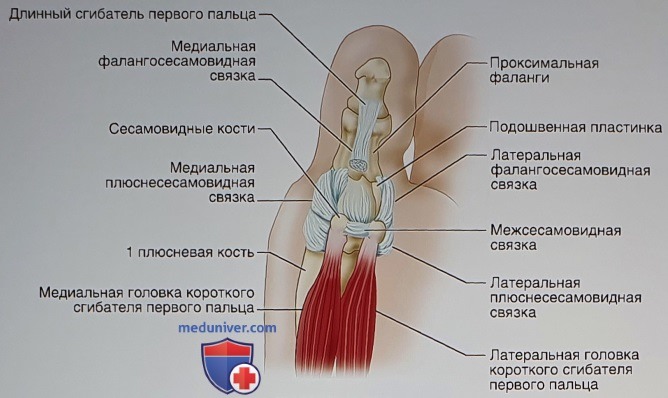

Перелом сесамовидной кости: Визуализация травмы и её лечение